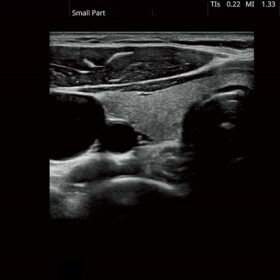

FUTUS features great imaging technologies to support a clear view and confident diagnoses.